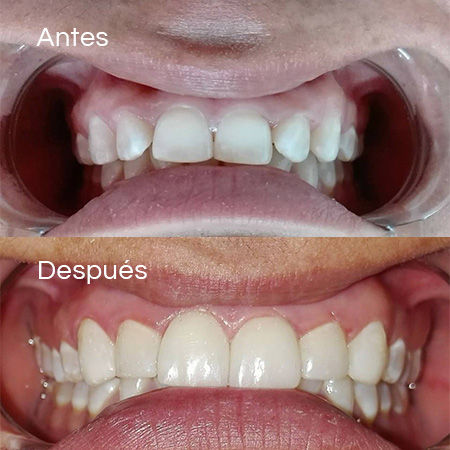

Before and After Gallery